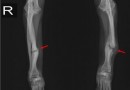

골절 후 부정 유합, 불유합

골절 후 부정 유합, 불유합(Malunion & nonunion of fracture) (정의)1. 유합 : 뼈가 붙는 상태를 말합니다. 2. 불유합 : 뼈가 붙지 않은 상태를 말하며, 즉 골절 후에 골절 부분의 치유 과정이 보이지 않는 경우로 골절선이…

경골과 비골 골절

경골과 비골 골절(Fracture of tibia & fibula) (정의)하퇴골(무릎밑부터 발목까지의 다리뼈)은 경골과 비골로 구성되어 있습니다. 경골(정강이뼈)은 내측에 있는 굵은 뼈이며 비골은 하퇴의 외측에 있는 가는 뼈입니다. 이 뼈들이 연속성을 잃은 …